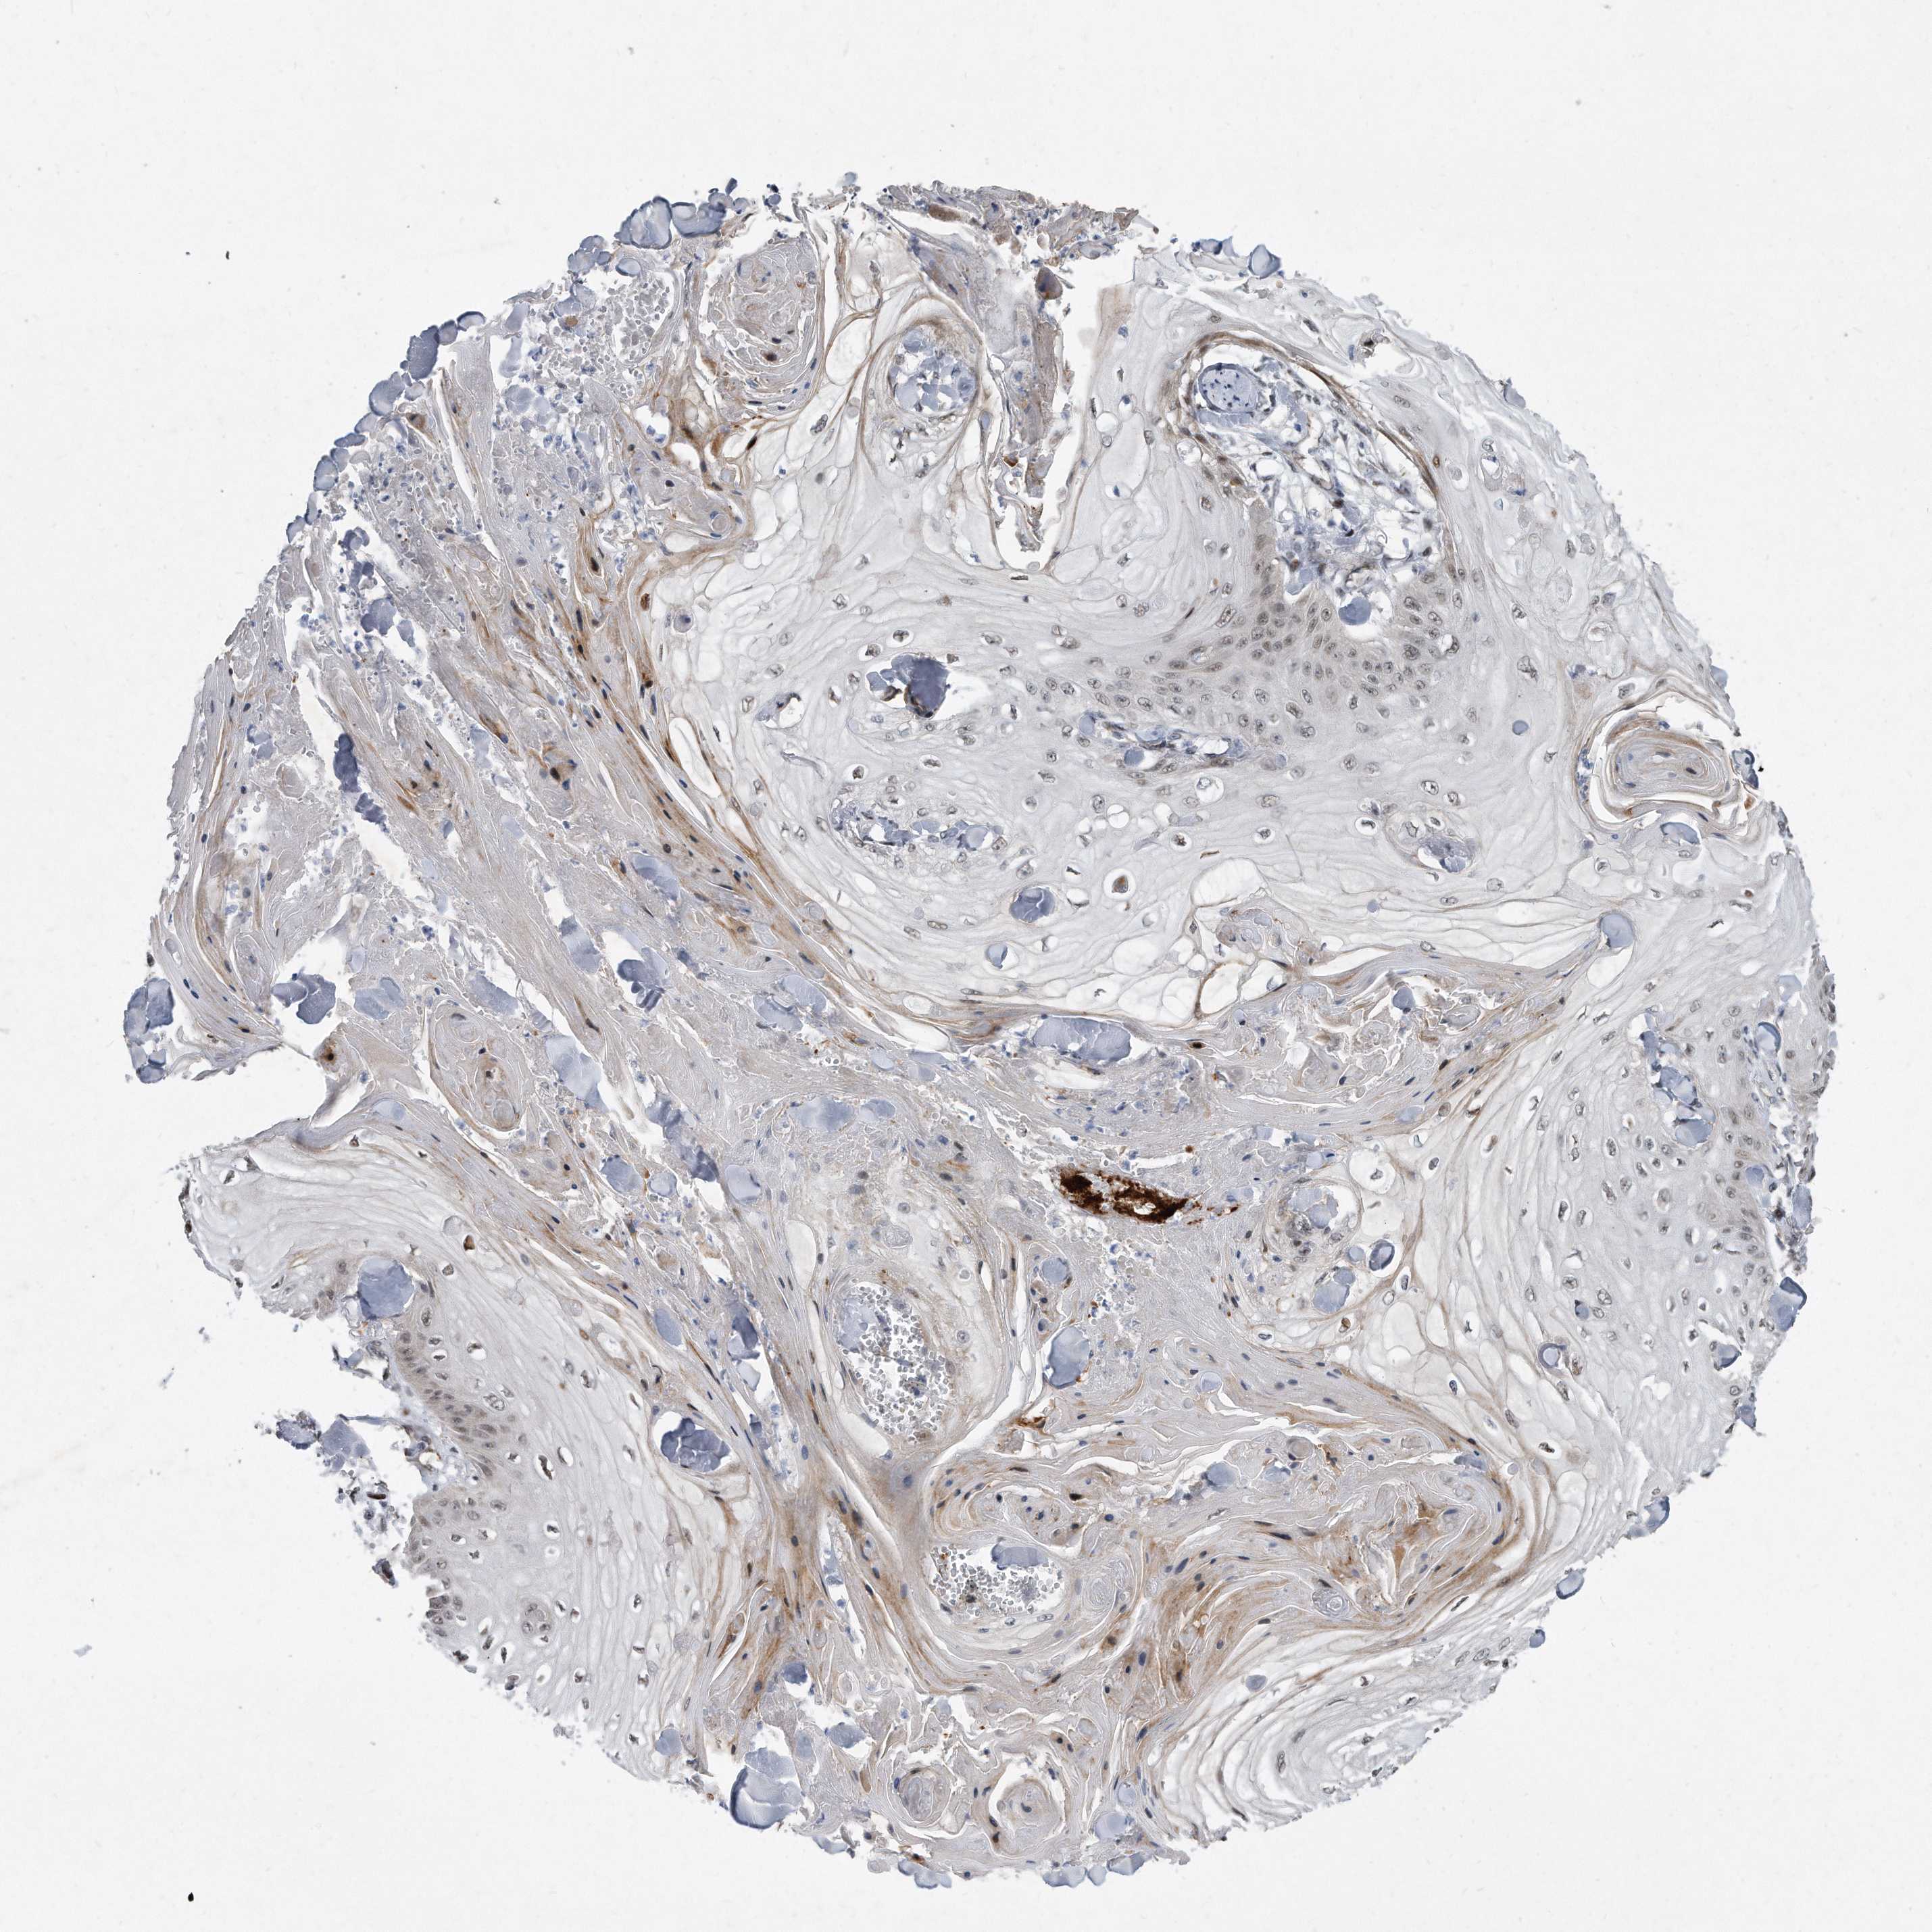

SKIN CANCER - Protein expressioni

A mouse-over function shows sample information and annotation data. Click on an image to view it in a full screen mode. Samples can be filtered based on level of antibody staining by selecting one or several of the following categories: high, medium, low and not detected. The assay and annotation is described here.

Antibody stainingi

Antibody staining in the annotated cell types in the current human tissue is reported as not detected, low, medium, or high, based on conventional immunohistochemistry profiling in selected tissues. This score is based on the combination of the staining intensity and fraction of stained cells.

Each image is clickable and will lead to virtual microscopy that enables deeper exploration of all samples and also displays staining intensity scores, fraction scores and subcellular localization as well as patient and tissue information for each sample.

Antibody HPA029888

Antibody HPA029889

Antibody HPA029890

Basal cell carcinoma